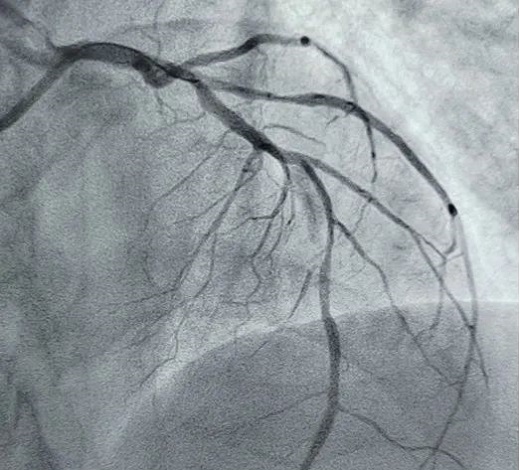

立即啟動綠色通道,急診冠脈造影,結(jié)果顯示前降支近段閉塞,血栓負(fù)荷較重,先后給予血栓抽吸及球囊擴(kuò)張,血流恢復(fù)正常。李桂武主任和劉興剛主任發(fā)現(xiàn)患者近段狹窄達(dá)70%,且中遠(yuǎn)段嚴(yán)重狹窄伴鈣化,此時不適合同期植入支架,如植入支架可能會引發(fā)血管破裂危及生命。當(dāng)務(wù)之急是快速評估出患者是否可以下手術(shù)臺,選擇擇期進(jìn)行處理,但僅根據(jù)造影結(jié)果又很難做出判斷,李桂武主任和劉興剛主任快速討論研究最后一致決定,給予患者行冠脈OCT檢查,明確病變性質(zhì)。

經(jīng)OCT檢查結(jié)果顯示:前降支中段鈣化,內(nèi)膜光滑,最小管腔面積僅為1.19 mm2。近段斑塊破裂,可見血栓影,最小面積為2.63mm2??蛇x擇先進(jìn)行抗栓治療,擇期處理冠脈病變。這讓張先生懸著的一顆心終于放下來。